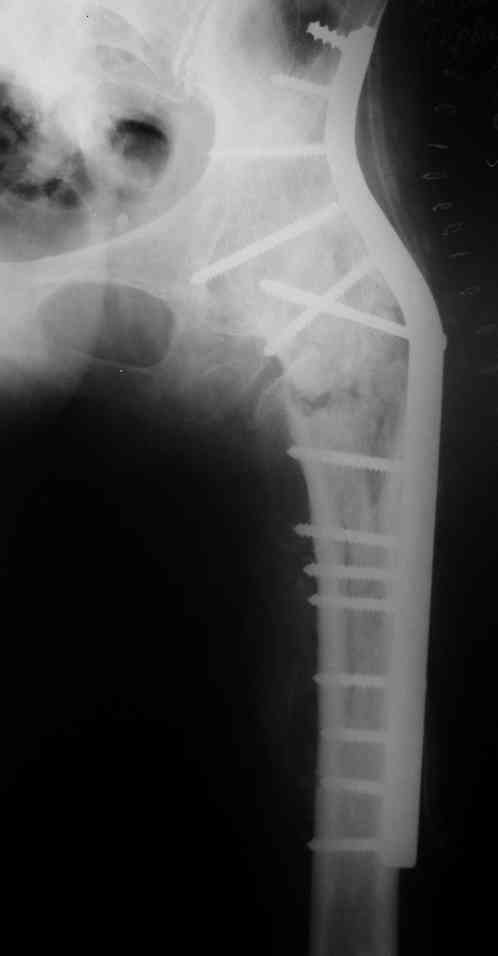

Re: перелом бедра+анкилоз тазобедренного сустава

Спасибо за совет и комментарии. Выбор остановили на длинной пластине DCP. Нам показалось, что в нашей ситуации так будет прочнее, по сравнению с клинковой пластиной или DHS.

Рентгенограмму полечили успешно. А какова длина послеоперационного рубца? Проводилась ли гемотрансфузия? На какой день после операции пациент начал ходить? А нагружать оперированную конечность?

Допустим, Вам правильно показалось, и прочность клинковой пластины или DHS, или такого или другого проксимального гвоздя, о чем писал Алексей Семенистый, была бы меньше. Но она была бы достаточной. По крайней мере для ранней нагрузки на ногу. А уж инвазивность уж точно была бы куда меньше, со всеми вытекающими плюсами.

Хотя, если выбор был между тазобедренной повязкой и сделанным остеосингтезом, наверно, был выбран оптимальный вариант.